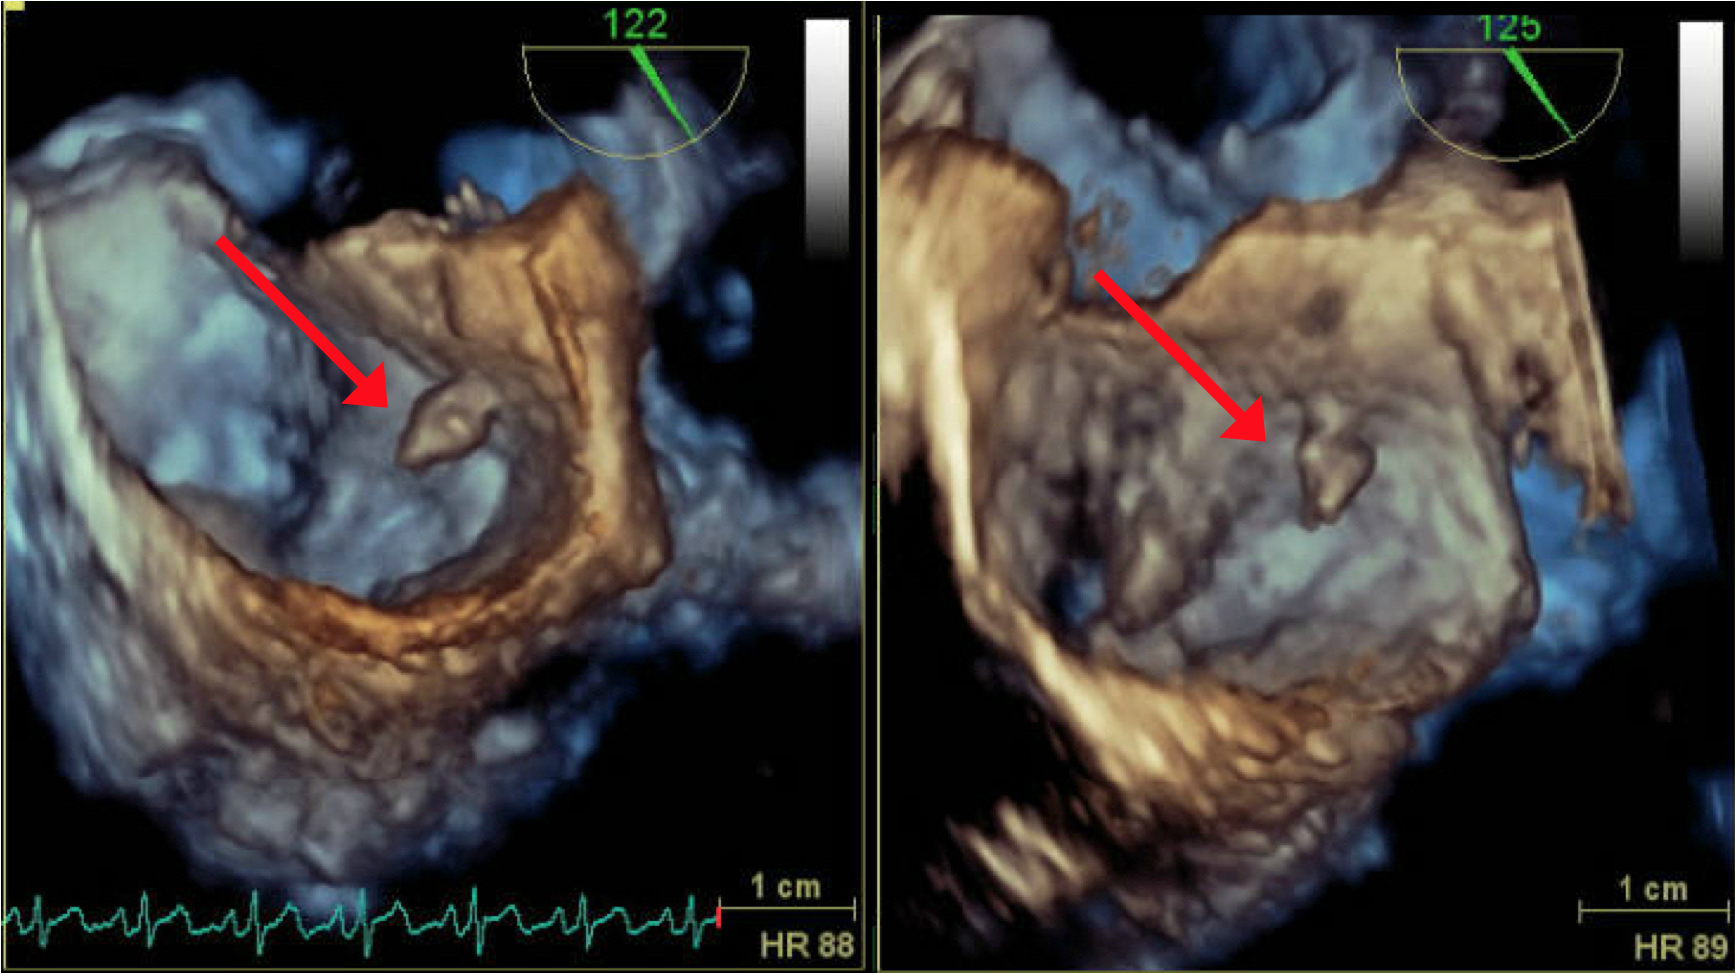

Patient was assessed with Transthoracic echocardiography (TTE) which showed mild left ventricular dysfunction (with ejection fraction of 40%) and a small mass attached to the lower interatrial septum (Figure 8). The findings were confirmed in transesophygeal echocardiography (TEE) study that described a pedunculated mass seen at the lower interatrial septum measured 0.8x0.6x0.5 cm (Figure 9 and 10) close to mitral aortic continuity. This was consistent with left atrial myxoma.

Figure 8: 2-D TTE in apical 4-chamber view and 2-D TEE showing small pedunculated myxomal mass measuring 0.8x0.6x0.5 cm attached to the lower interatrial septum on left atrial side.

Figure 9: 3-Dimantional TEE showing the myxomatous remnant attached to the interatrial septum near the base atrial mitral leaflet.